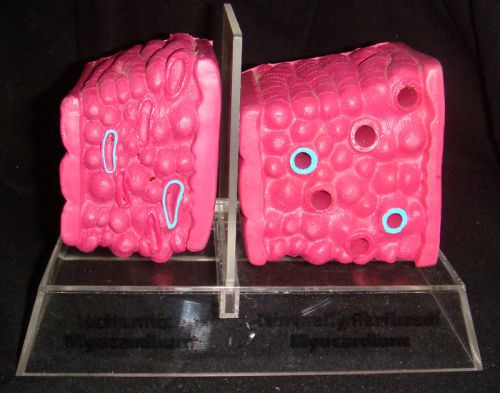

Normal & Ischemic Cardiac Muscle Anatomical Model Heart